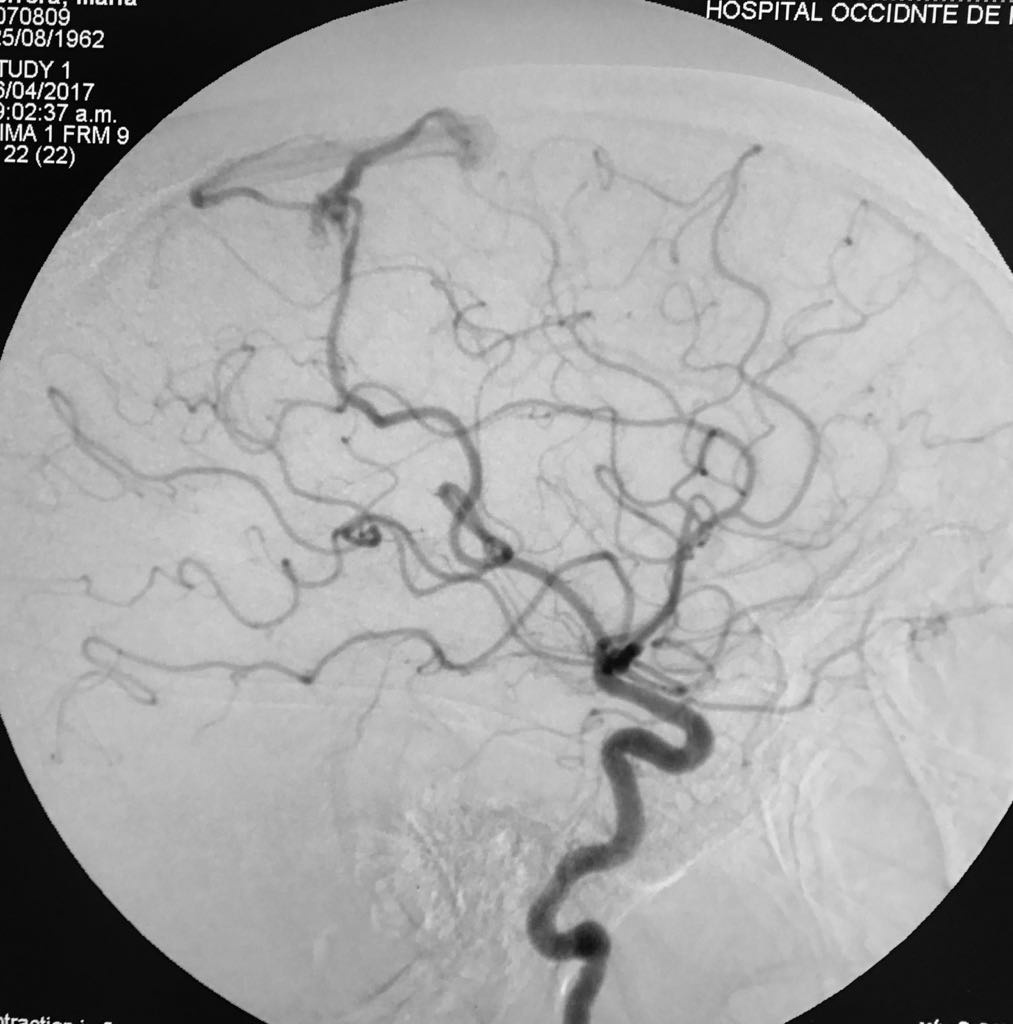

Somos una empresa enfocada en la atención en salud humana por medio del uso imágenes para ver diagnosticos y tratamientos de las diversas patologías con el uso de técnicas mínimamente invasivas en el territorio colombiano en el sector público y privado en búsqueda de una atención oportuna y de calidad a cada uno de nuestros pacientes.